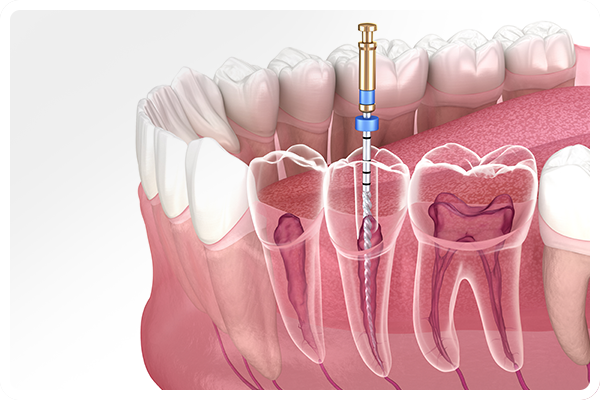

根管治療について

歯の根をしっかり治して

大切な歯をできるだけ残す治療

加古郡播磨町・加古川市・明石市のエリアで「むし歯が痛い」「噛むと響く」などのお悩みがあるかたは、根の中に炎症が起きている可能性があります。当院では、精密な根管治療により、むし歯が進行した歯でもできるだけ抜かずに残す治療を心がけています。歯の根の治療は時間と技術を要しますが、再発を防ぎ、歯の寿命を延ばすためには欠かせません。痛みが続く場合や治療後も違和感がある場合は、お早めにご相談ください。

精度を上げるための設備

ニッケルチタンファイル

しなやかで折れにくいニッケルチタン製の器具を使うことで、複雑な根の形にも対応し、効率的かつ安全に感染部位を除去できます。

根管拡大装置

根管の形状に合わせて均一に広げることで、薬剤が奥まで届きやすくなります。手作業よりもスムーズで精度の高い処置が可能です。

根管長測定器

根の長さを正確に測定する機器を使用し、必要な部分だけを処置します。無駄に削りすぎることなく、歯の寿命を守ることにつながります。